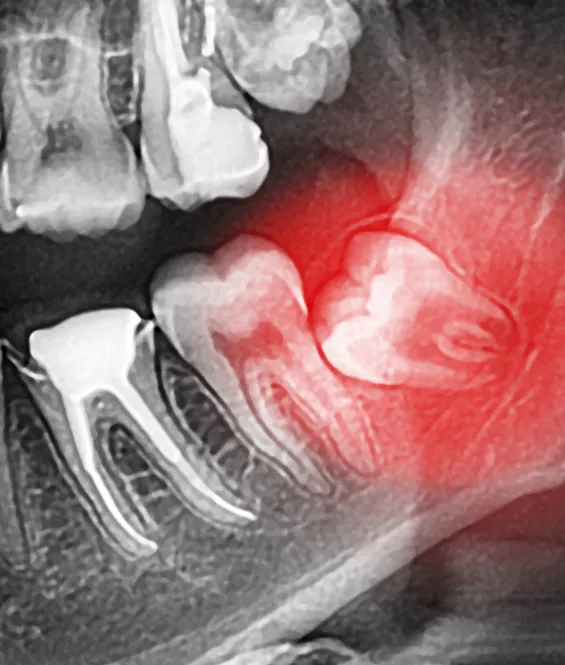

The wisdom teeth are a third set of large molars. They are usually the last of the adult teeth to grow in. For many patients, there is no room in the jaw for the wisdom teeth to emerge correctly, and they can become impacted or misaligned. If we detect that this is happening, we will recommend extraction of the wisdom teeth before they erupt through the gums.